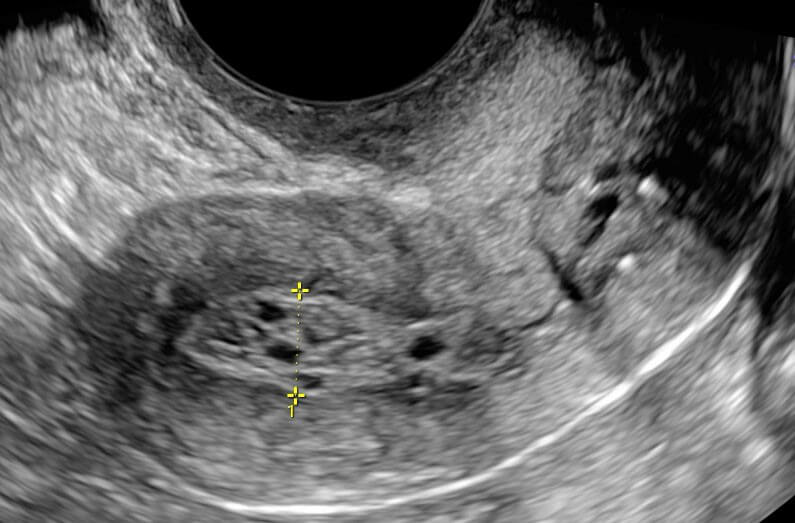

A ultrassonografia transvaginal (USG-TV) é geralmente a primeira escolha para a avaliação do endométrio. Entretanto, utiliza-se outras técnicas de imagem, como a sonohisterografia com infusão salina (SIS), histerossalpingografia, tomografia computadorizada e ressonância magnética, como complementares ou confirmatórias, quando necessário.

Para evitar a superestimação da espessura endometrial durante a USG-TV, realiza-se a medição em corte sagital da linha média, evitando-se imagens oblíquas ou próximas dos cornos uterinos. Um indicativo de que o plano está corretamente posicionado na linha média é a visualização contínua do eco endometrial com o canal endocervical.

Sinais ultrassonográficos de câncer de endométrio

Em pacientes na pós-menopausa, um aumento na espessura endometrial observado na ultrassonografia transvaginal associa-se a um maior risco de neoplasia maligna em comparação com alterações benignas — sendo que uma espessura inferior a 4 mm indica baixo risco de acometimento endometrial.

Como já mencionado, a espessura endometrial é aferida com o útero em corte sagital, sendo registrada a medida da dupla camada endometrial, desconsiderando-se qualquer presença de líquido na cavidade uterina.